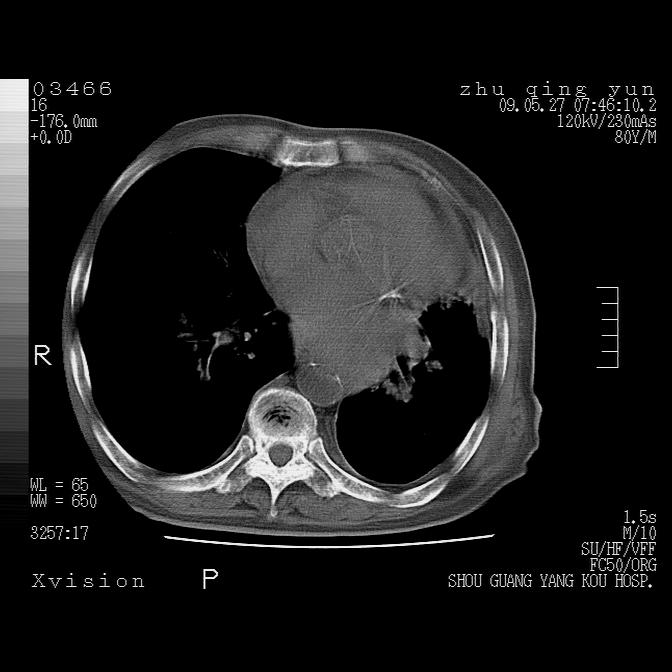

病人男性,年龄80,气喘来院,其他病史不太详细,1月前有过恶心,呕吐,在当地人民医院做过钡餐,诊断胃炎,

1)考虑左肺中央型肺癌并阻塞性肺炎,后下纵隔受侵伴纵隔淋巴结转移。2)双侧少量胸腔积液,胸膜增厚。3)心包积液。

左肺下叶见多发片状及结节状病灶,左肺基底段支气管闭塞,纵隔内见多发淋巴结肿大,纵隔向左侧移位,左侧胸廓变小。应该是左肺下叶中心型肺癌,纵隔淋巴结转移,左侧肺内转移,左肺基底段肺不张,阻塞性肺炎。

1)考虑左肺中央型肺癌并左肺下叶阻塞性肺炎、不张;左胸膜腔积液、心包积液、纵隔淋巴结转移;癌肿累及左心房。2)左心室大。冠状动脉壁钙化斑。